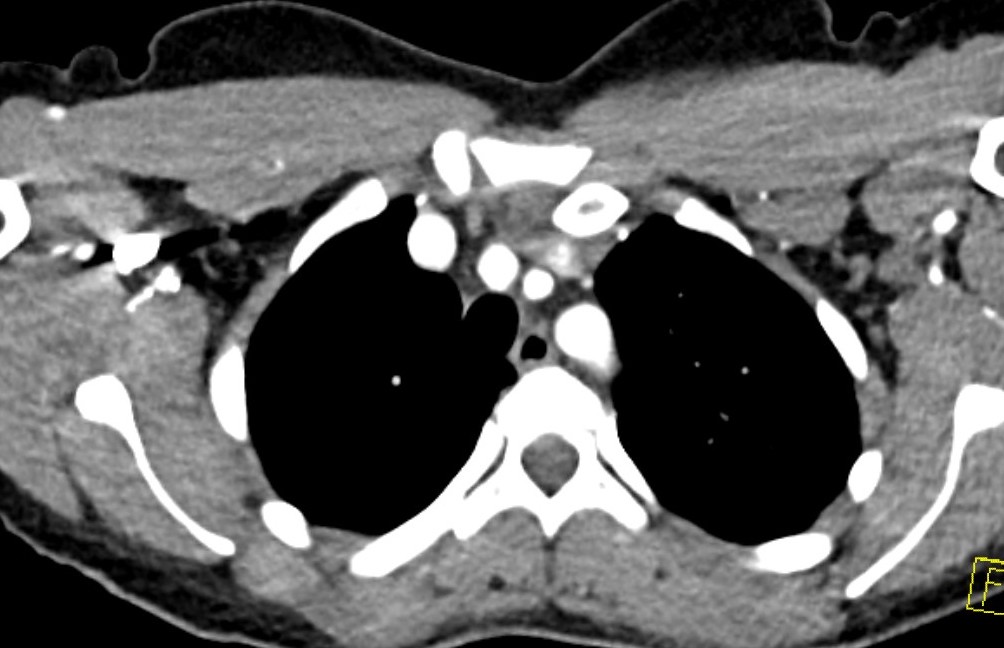

Left posterior SCJ dislocation with pre- and post angiogram

Left posterior SCJ dislocation with pre- and post angiogram

Severe left posterior SCJ dislocation with subclavian vein compression